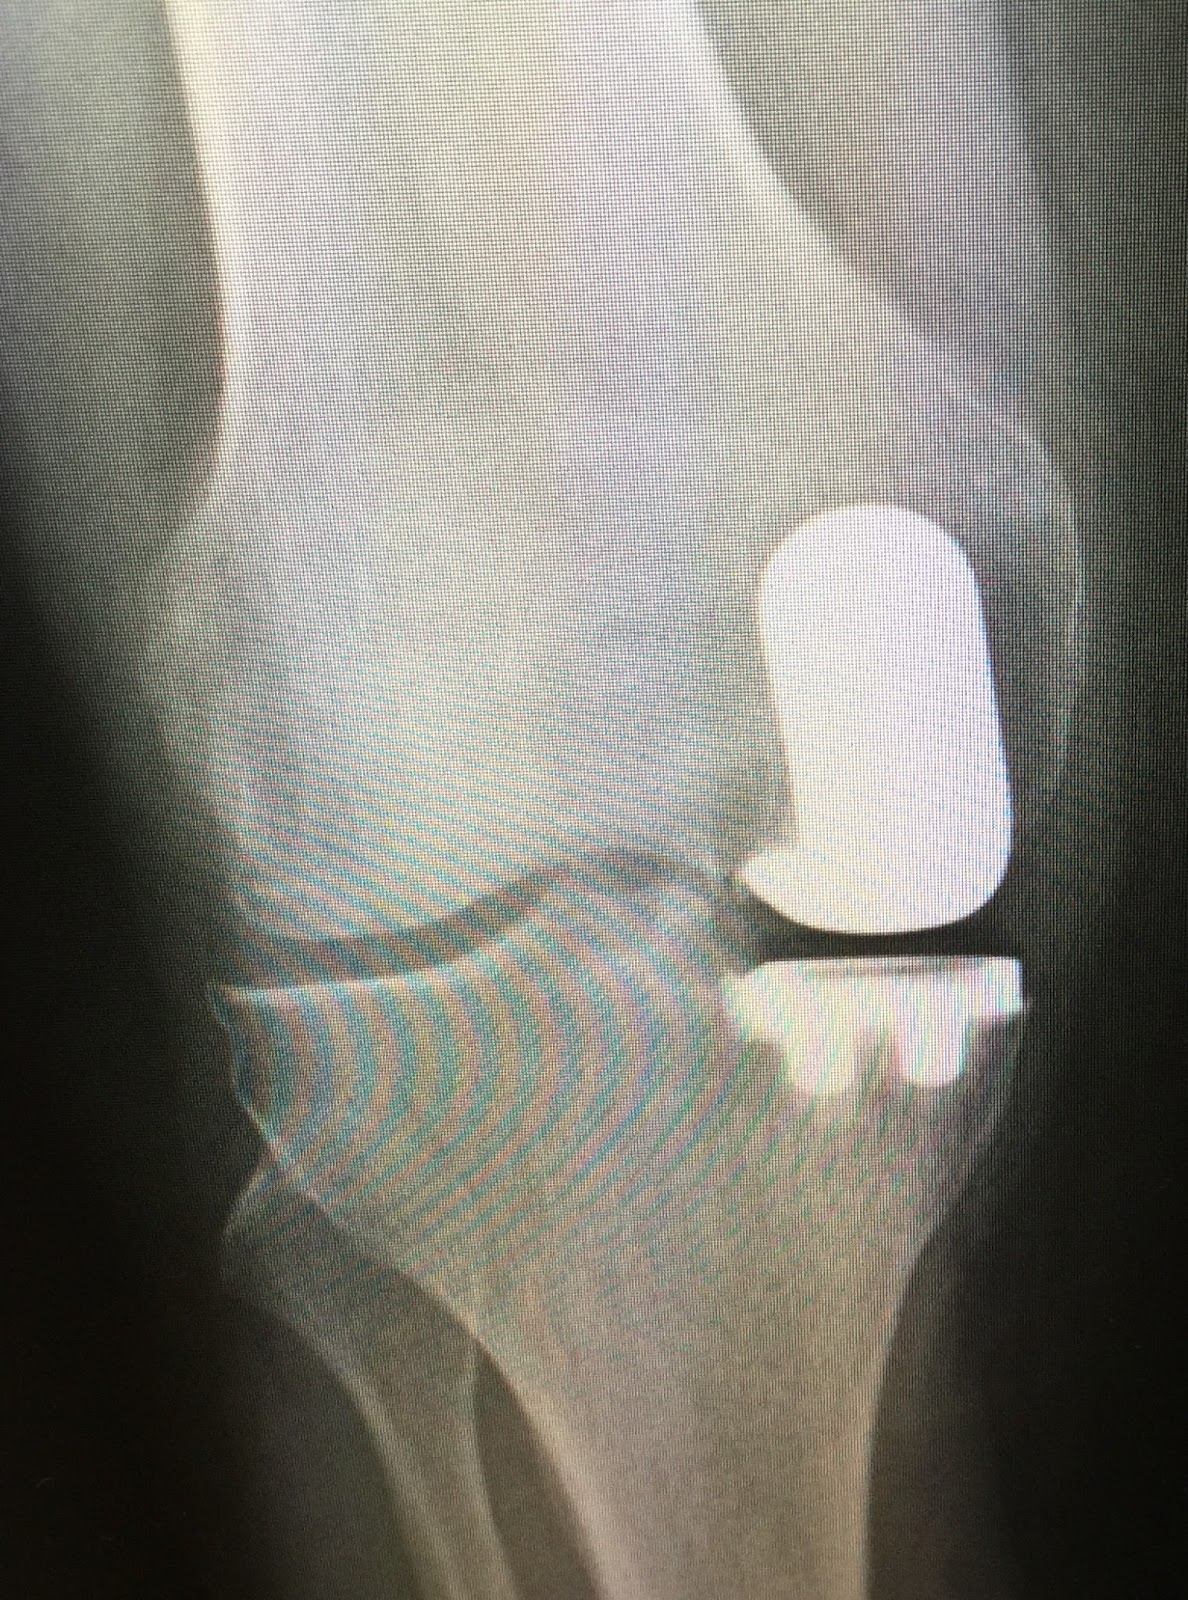

Unicompartmental Knee Replacement Xray . Web unicompartmental knee arthroplasties (uka) or replacements (ukr) are orthopaedic procedures where either the. In contemporary literature, there is emerging and solid evidence that uka, when performed in correctly selected cases, holds multiple advantages for patients. Web unicompartmental knee arthroplasty (uka) has a long history, but has not been established as a treatment at the same level with total knee arthroplasty (tka). Web in unicompartmental knee replacement (also called partial knee replacement) only a portion of the knee is resurfaced with metal and plastic components. Web oxford unicompartmental knee replacement glide over each other as the knee bends. Web unicompartmental knee arthroplasty (uka) is a surgical technique used for the treatment of osteoarthritis in one compartment of the. Web unicompartmental knee arthroplasty is a surgical option for knee arthritis when only one compartment of the knee is involved.

Web unicompartmental knee arthroplasties (uka) or replacements (ukr) are orthopaedic procedures where either the. In contemporary literature, there is emerging and solid evidence that uka, when performed in correctly selected cases, holds multiple advantages for patients. Web unicompartmental knee arthroplasty (uka) is a surgical technique used for the treatment of osteoarthritis in one compartment of the. Web oxford unicompartmental knee replacement glide over each other as the knee bends. Web in unicompartmental knee replacement (also called partial knee replacement) only a portion of the knee is resurfaced with metal and plastic components. Web unicompartmental knee arthroplasty is a surgical option for knee arthritis when only one compartment of the knee is involved. Web unicompartmental knee arthroplasty (uka) has a long history, but has not been established as a treatment at the same level with total knee arthroplasty (tka).

Unicompartmental Knee Replacement Xray In contemporary literature, there is emerging and solid evidence that uka, when performed in correctly selected cases, holds multiple advantages for patients. Web unicompartmental knee arthroplasty (uka) has a long history, but has not been established as a treatment at the same level with total knee arthroplasty (tka). Web unicompartmental knee arthroplasty is a surgical option for knee arthritis when only one compartment of the knee is involved. Web in unicompartmental knee replacement (also called partial knee replacement) only a portion of the knee is resurfaced with metal and plastic components. Web oxford unicompartmental knee replacement glide over each other as the knee bends. Web unicompartmental knee arthroplasty (uka) is a surgical technique used for the treatment of osteoarthritis in one compartment of the. In contemporary literature, there is emerging and solid evidence that uka, when performed in correctly selected cases, holds multiple advantages for patients. Web unicompartmental knee arthroplasties (uka) or replacements (ukr) are orthopaedic procedures where either the.